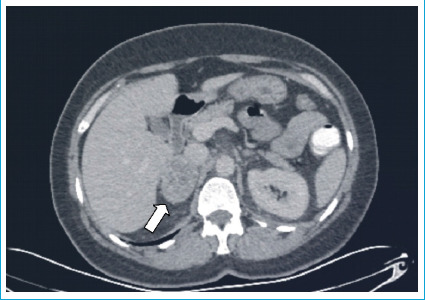

嗜铬细胞瘤是一种起源于肾上腺的罕见肿瘤,以分泌儿茶酚胺为特征。由于高血压危象与儿茶酚胺释放相关,嗜铬细胞瘤患者的手术治疗是有风险的。在这个病例报告,腹腔镜阑尾切除术急性阑尾炎患者谁有嗜铬细胞瘤将提出。女性,49岁,腹痛。体格检查显示右下腹有防守和反弹。患者在调查中有白细胞增多,腹部计算机断层扫描显示急性阑尾炎和5厘米右肾上腺肿块的迹象。六个月前内分泌科的腹部磁共振成像显示右肾上腺有一个39x32毫米的肿块,尿儿茶酚胺水平升高。据了解,该病人在此期间没有参加后续预约。患者接受内分泌科会诊,并进行了紧急腹腔镜阑尾切除术。患者于术后第2天出院,未出现任何并发症。患者转至内分泌科,开始进行嗜铬细胞瘤手术的术前准备。在紧急情况下,诊断为嗜铬细胞瘤的患者可以在适当的术前准备下进行紧急手术。

Pheochromocytoma is a rare tumor originating from the adrenal gland, characterized by the secretion of catecholamines. Due to the risk of hypertensive crises associated with catecholamine release, surgical procedures in pheochromocytoma patients are risky. In this case report, laparoscopic appendectomy for acute appendicitis in a patient who has pheochromocytoma will be presented. A 49-year-old female patient presented with abdominal pain. Physical examination showed guarding and rebound in the right lower quadrant. The patient, who had leukocytosis in the investigations, showed signs of acute appendicitis and a 5 cm right adrenal mass on the abdominal computed tomography. A previous abdominal magnetic resonance imaging by the endocrinology department six months ago revealed a 39x32 mm mass in the right adrenal gland and elevated urinary catecholamine levels. It was learned that the patient had not attended follow-up appointments during this period. The patient was consulted by endocrinology and an emergency laparoscopic appendectomy was performed. The patient, discharged on the 2nd day after surgery, did not experience any complications. The patient was referred to endocrinology, and preoperative preparations for pheochromocytoma surgery were initiated. In cases of emergency in patients diagnosed with pheochromocytoma emergency surgery can be performed with appropriate preoperative preparation.